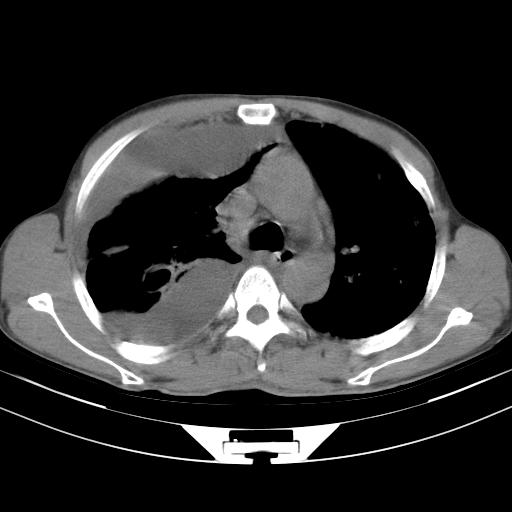

男性,44岁,结核病史多年。现胸闷气短,咳嗽,偶咳血。

右侧胸腔积液

右肺下叶不张

双肺多发结节影最分空洞形成考虑占位不除外结核

双肺陈旧性病变

1、右侧大量胸腔积液伴右肺压缩性膨胀不全,建议抽液治疗后复查 2、两肺继发性tb伴空洞形成。

1)两肺继发性肺结核伴空洞形成,左肺多发性结核球。2)右侧大量胸腔积液伴右肺部分膨胀不全。3)纵隔淋巴结肿大。

吉大一院胸水抽检结果:结核性胸水